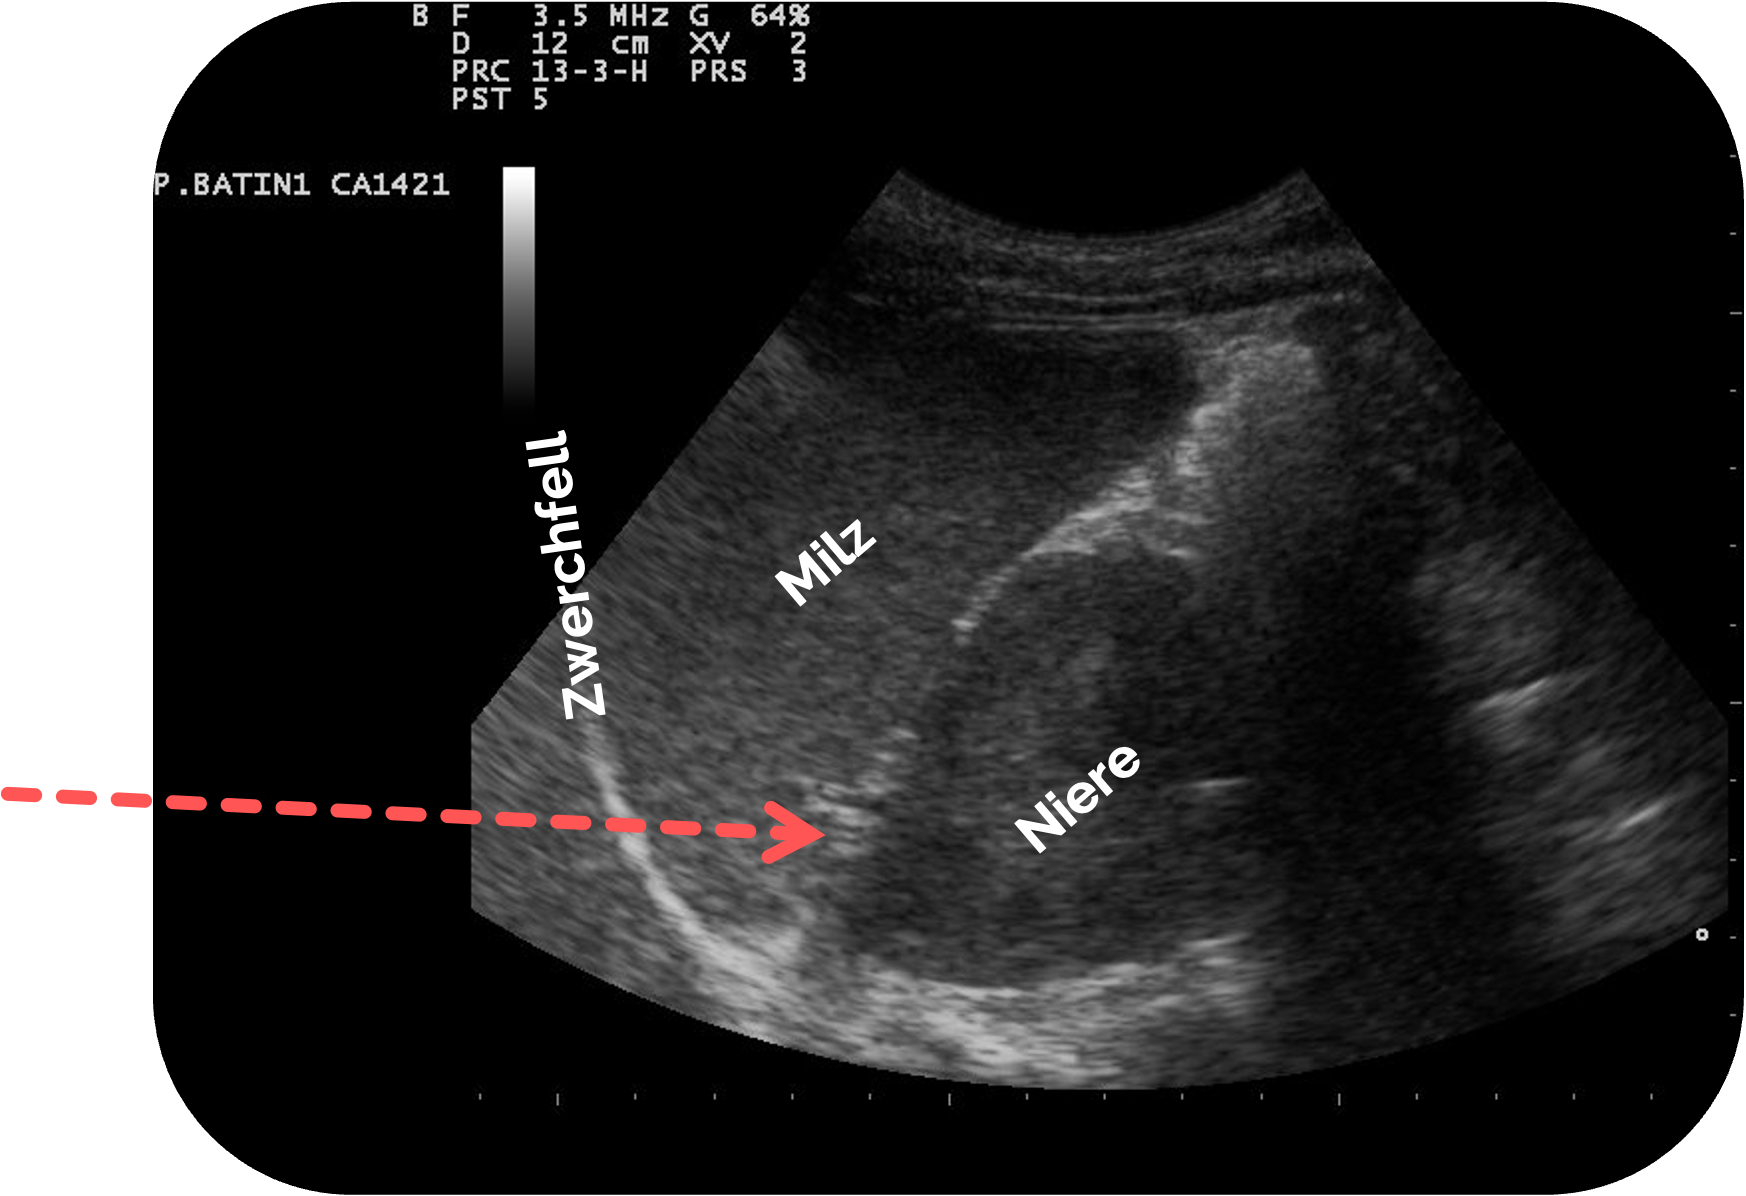

Schritt 2: Orientierung - Anatomische Grundstrukturen

- Milz im oberen Bildanteil, homogen und echoreicher als Niere

- Linke Niere etwas kaudaler und dorsal

- Zwischen Milz und Niere liegt der Koller-Pouch (splenorenaler Rezessus) (siehe Pfeil)

- Zwerchfell

als echoreiche Linie oberhalb der Milz - Luftartefakte der linken Lunge

Ultrasound image of spleen 110318090022 0905570.jpg, Nevit Dilmen, CC BY-SA 3.0, https://creativecommons.org/licenses/by-sa/3.0, via Wikimedia Commons. Es wurden die Markierung und die Beschriftungen ergänzt.